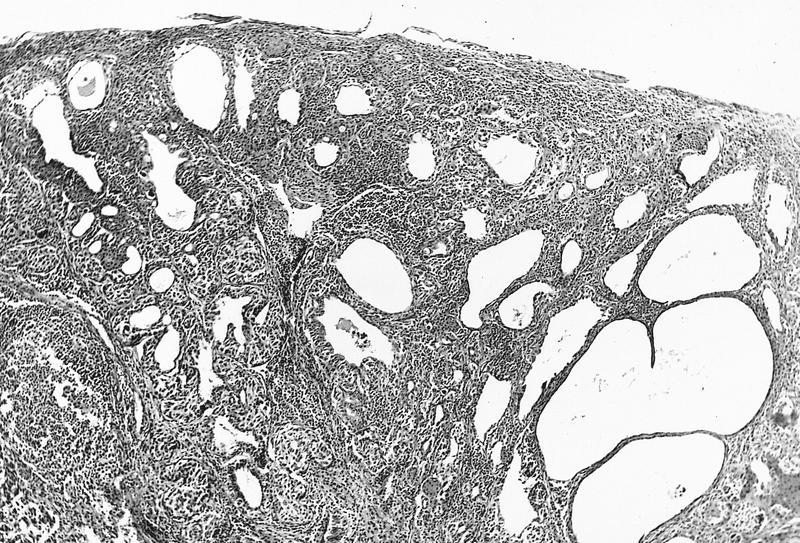

- Nevomelanocytes organized into intraepithelial nests of oval cells (type A), sheets of oval to cuboidal cells (type B), and spindled cells in subepithelium (type C)

- Often (50%) with solid and prominent cystic inclusions of conjunctival epithelium and chronic inflammatory infiltrate

- Compound (70 - 78%):

- Most common, nevi cells in epithelium and subepithelial connective tissue

- Cells have cysts lined by cuboidal and goblet cells and intranuclear inclusions

- May have large pigmented cells with prominent basophilic nucleoli

- Usually mixed inflammatory cells

Cystic compound nevus: